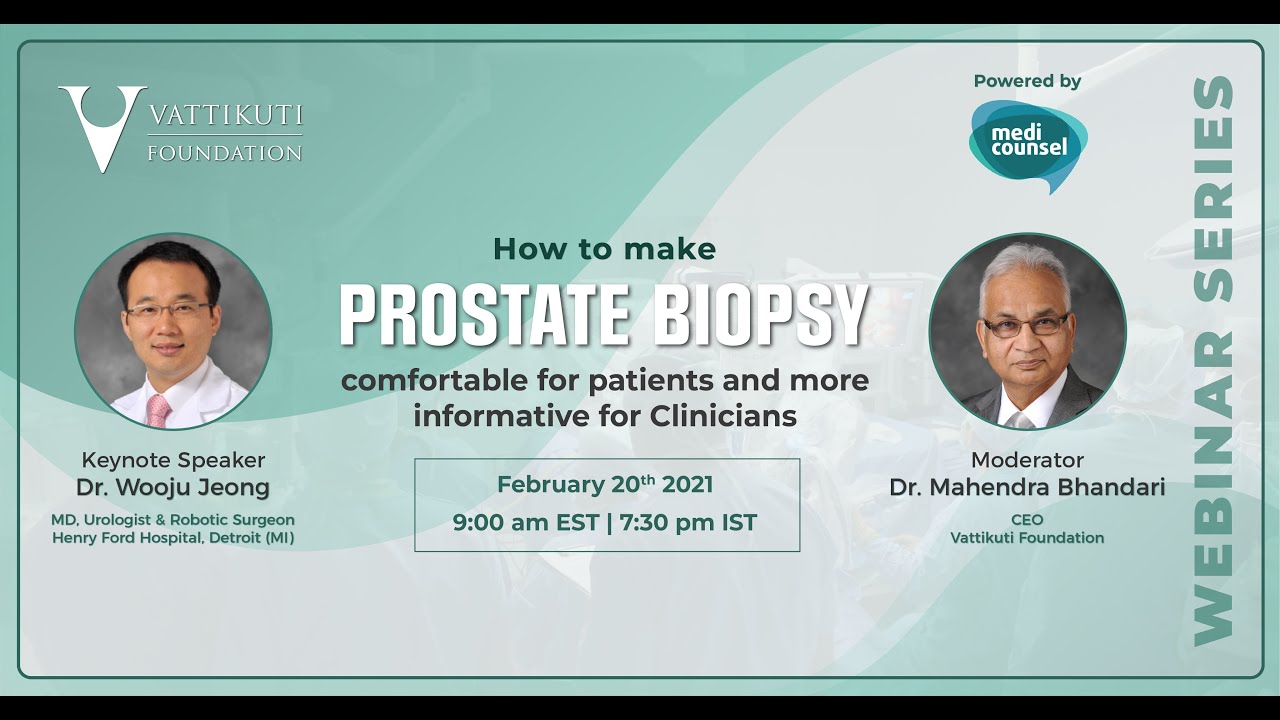

How to make prostate biopsy comfortable for patients and more informative for Clinicians

Masterclass, Robotics, Urology ';